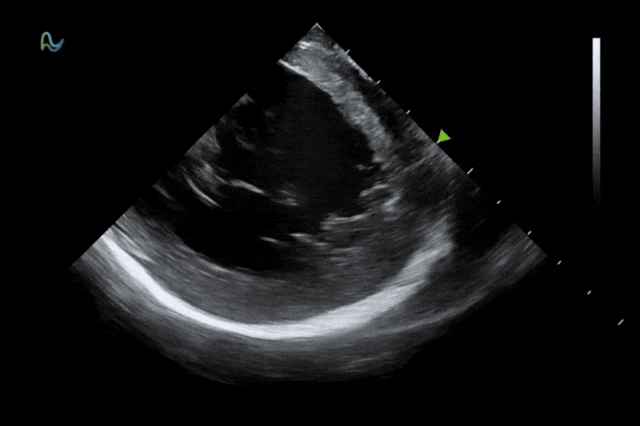

本次获批的ICE导管在全球首次采用了80阵元大孔径高密度探头设计,较传统普通的64阵元产品大幅度提升了成像分辨率、成像深度和图像对比度,可清晰辨识心脏细微结构和血流,为复杂手术提供更可靠的超声成像支持。同时,8F导管凭借更小的外径,显著提升导管通过性和操控性,对病人创伤更小,尤其适合血管条件受限或小心脏患者;10F导管则凭借其优质的成像质量,为复杂心脏介入手术提供精准的影像引导。